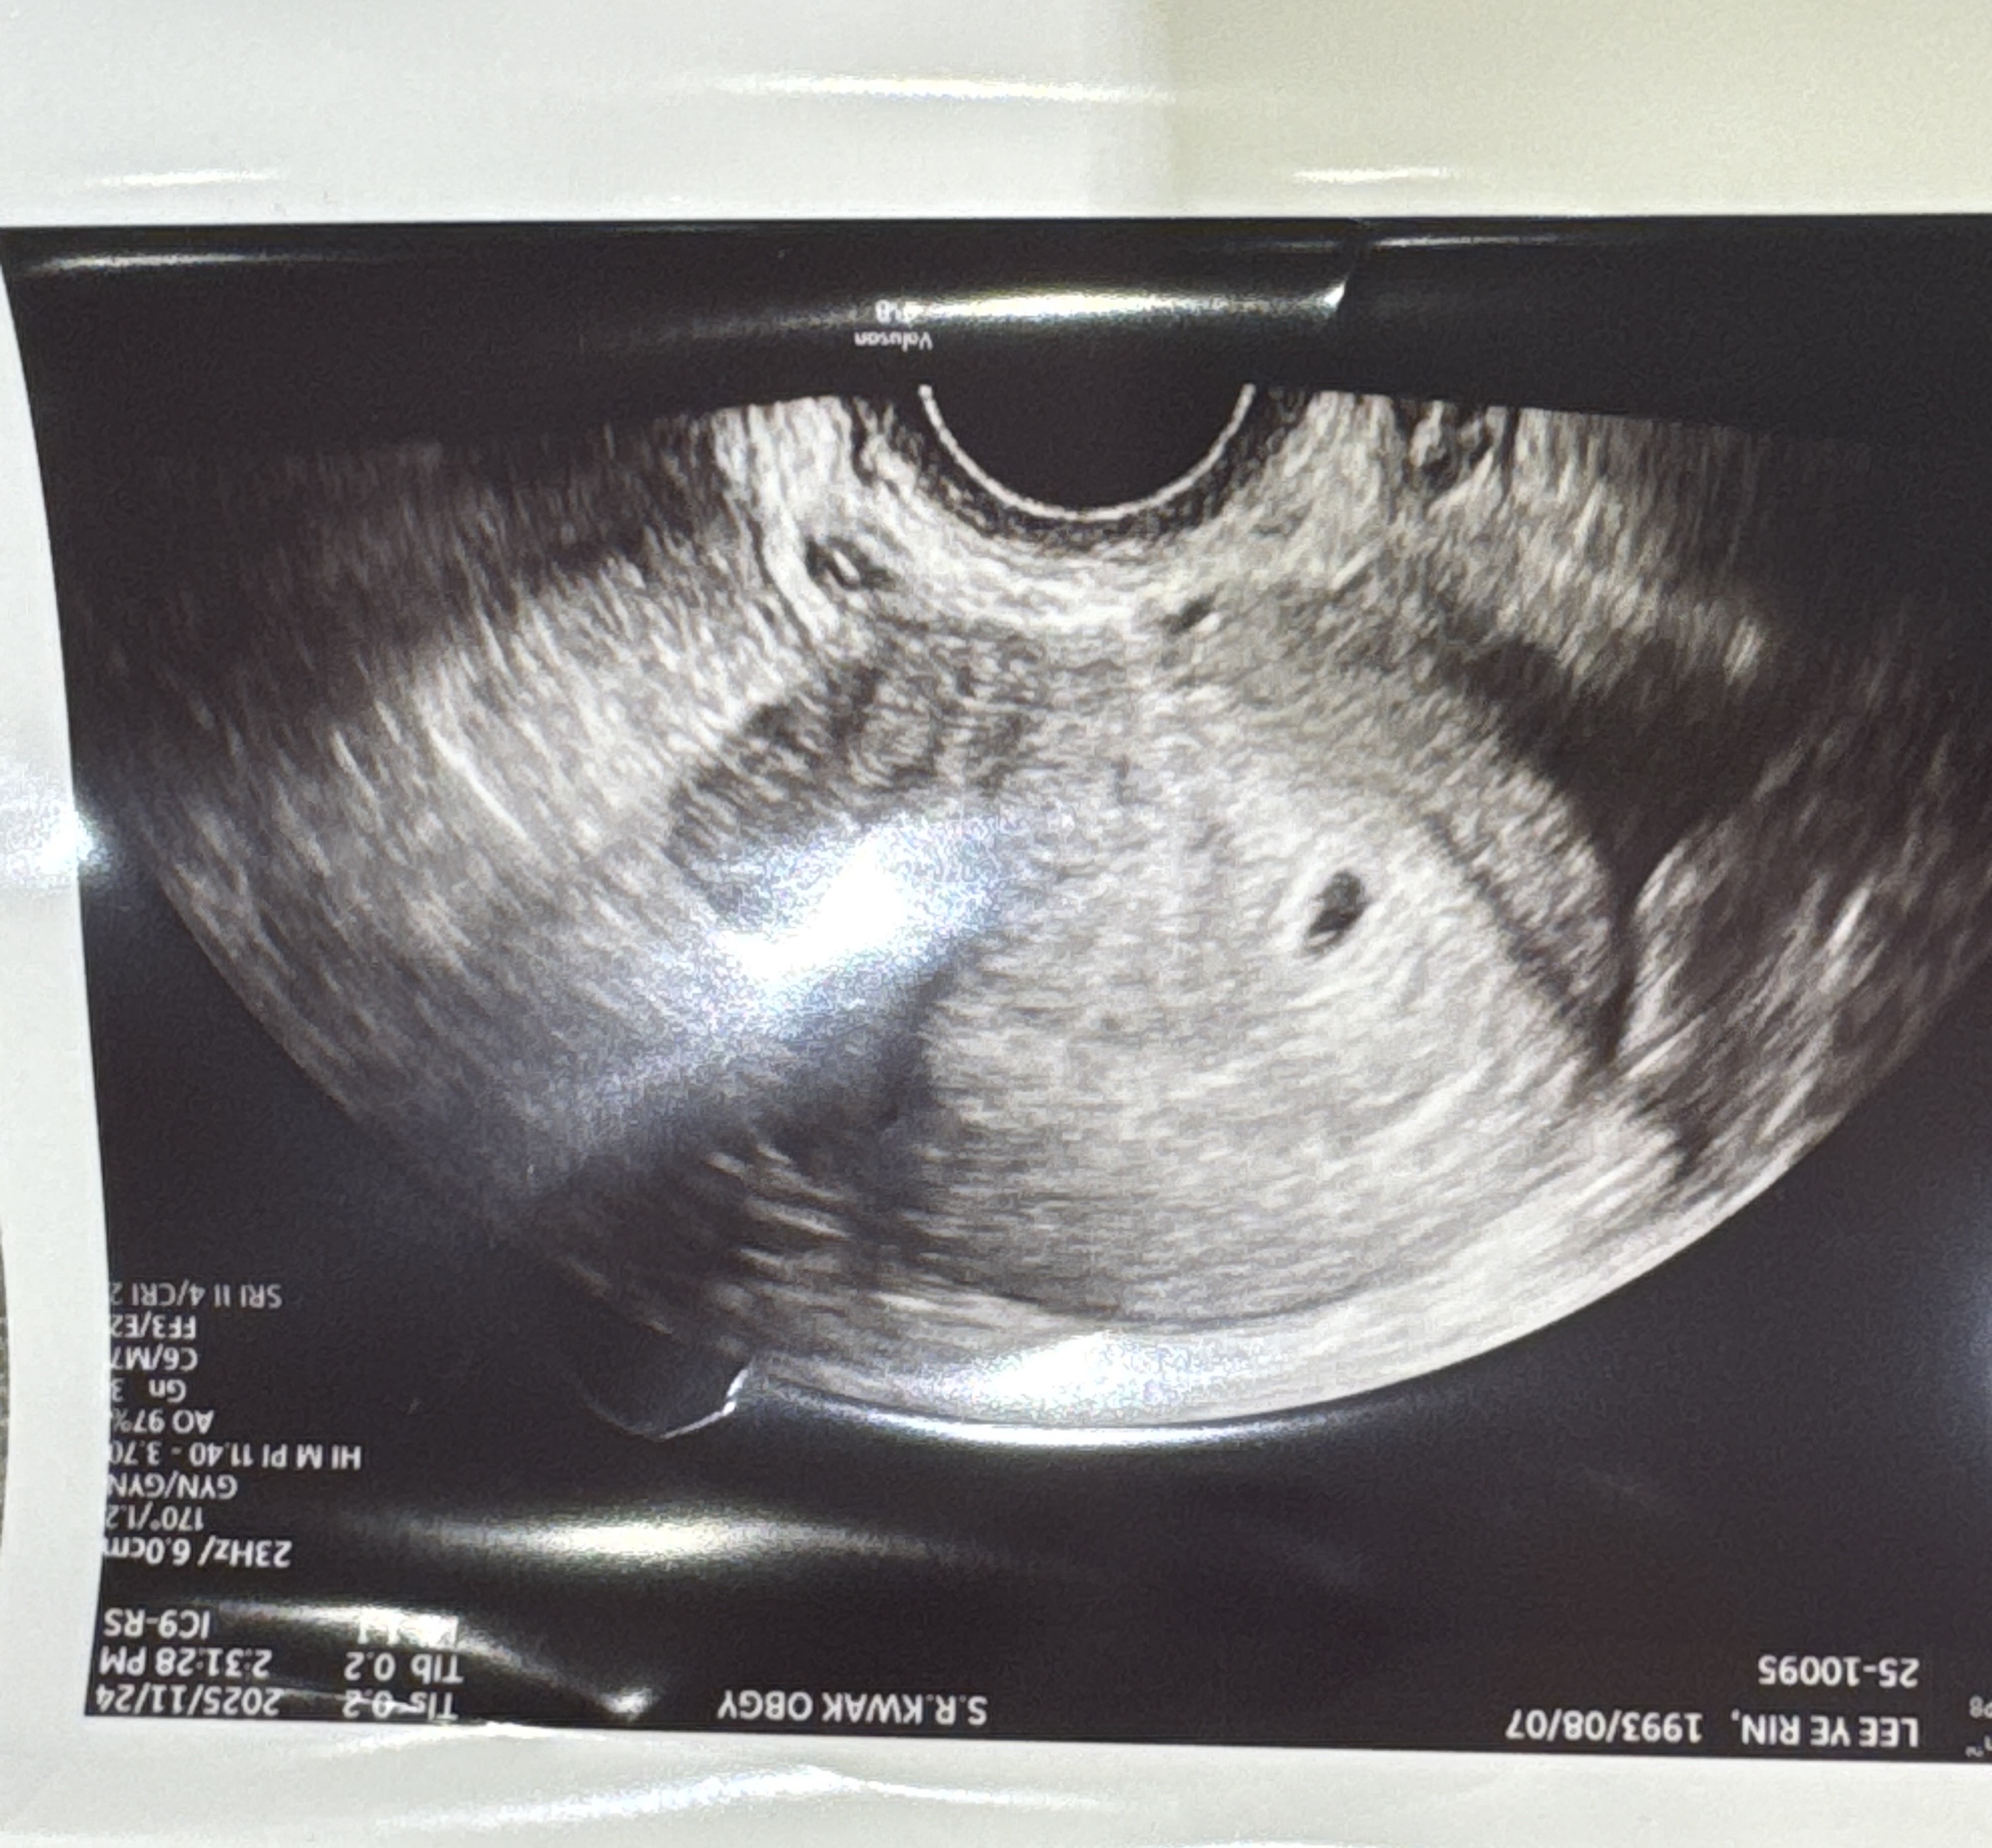

4주5일차 드디어 아기집 보고왔어요 ㅠ 저 하얗게 보이는게 혹시 난황일까요? 이주후에 오라는데 넘 초초하네요오

2주후에 난황보일거에요. 지금은 아기집만 있는게 당연해요~